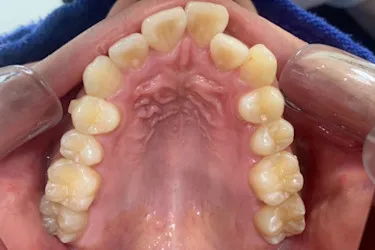

人と接する機会が多く、第一印象を大切にしたいと考え、写真写りや笑顔への自信を高めたいという思いから矯正を決意された矯正当時学生だった22歳男性の H.S.様に、スマイルモア矯正を選んだ理由を伺いました。

| 詳細情報 | |

|---|---|

| 費用 | 360,000円(税込396,000円) |

| 治療期間 | 11ヶ月 |

| 治療内容 | マウスピースを用いた歯列矯正 |

| 追加処置 | IPR |

以前よりも歯並びが改善され、人とコミュニケーションをとることに自信がつきました。 「スマイルモア」という名前の通り、笑顔に自信がついたことで今までよりも口を開けて笑う機会も増えました。 矯正期間が年単位だったのですぐに変化があったわけではないですが、綺麗な仕上がりに満足しています。